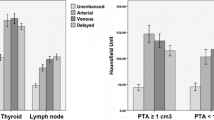

The following parameters were considered in the normal thyroid, parathyroid and lymph nodes. The maximum peak enhancement (HUmax) is defined as the maximum concentration of contrast agent over time and was measured in the region of interest. It is expressed in Hounsfield units (HU). The time to peak (TTP) is defined as the time at which HUmax is reached. It is expressed in seconds (s). The mean slope of increase (MSI) corresponds to the steepness of the enhancement curve of a given region of interest. It is expressed in percent (%). An overview of these different values is provided in Table 2.

Enhancement (Y-axis) over time (X-axis) curve. The curve for the suspected parathyroid (yellow) is steeper than the curve for the thyroid (green), and the peaks for the artery (red) and vein (blue) are higher in comparison. An artifact due to motion is observed at 34 s with suboptimal HU measurement of the small parathyroid lesion. The graph also demonstrates venous wash-out of the suspected parathyroid (50–70 s). Additionally, note the lack of prominent difference in enhancement between the adenoma and the thyroid at 25 s after administration of contrast. The purple curve indicates slow continuous enhancement of a lymph node

Eleven out of 15 detected adenomas demonstrated a higher peak enhancement in the arterial phase than that in normal thyroid tissue (arterial wash-in). Four out of 15 adenomas had a slightly lower peak enhancement in the arterial phase than that in normal thyroid tissue. These four adenomas showed a lower enhancement than the thyroid in the later venous phases (venous wash-out). The enhancement pattern of the lymph nodes differed from the parathyroid and thyroid tissue with lower maximum enhancement (mean HUmax 102 HU). These lesions did not demonstrate a significant wash-in or wash-out of contrast.

The mean TTP for parathyroid adenomas was calculated at 30.8 s (interval 26–42 s). The mean TTP for normal thyroid tissue was calculated at 32.3 s (interval 26–45 s). The TTP for parathyroid adenomas was observed significantly earlier (p-value 0.008). The MSI was significantly steeper for the adenomas (29.8% vs 22.2%, p-value 0.012).

We found a statistically significant difference in the TTP and MSI between parathyroid and thyroid tissue, with parathyroid adenomas showing a steeper curve and becoming enhanced on average 1.5 s earlier. Since the interval for the TTP for parathyroid adenomas in our study varied between 26 and 42 s after contrast administration, arterial enhancement was less conspicuous with a single arterial phase 25 s after contrast administration (the most common protocol found in the literature).

Cervical lymph nodes are a known mimicker of parathyroid adenomas. Based on their slow and continuous enhancement, these structures can be readily differentiated from parathyroid adenomas. In the case of cervical lymph node metastasis, we could expect an alteration of this enhancement pattern. In a patient presenting with PHPT symptoms, lymph node metastasis would have to be considered an incidentaloma and thus proven to be rare. Localized spread from a parathyroid carcinoma could be considered an associated possibility; however, this disease is also increasingly rare (reported incidence 0.5 to 5% of primary hyperparathyroidism cases) [71]. Another known mimicker of a parathyroid adenoma is ectopic thyroid tissue. It can be suggested that this ectopic thyroid tissue would behave in a similar way to normal thyroid tissue and thus differ from parathyroid adenomas. As we did not come across a relevant case, this remains speculation.